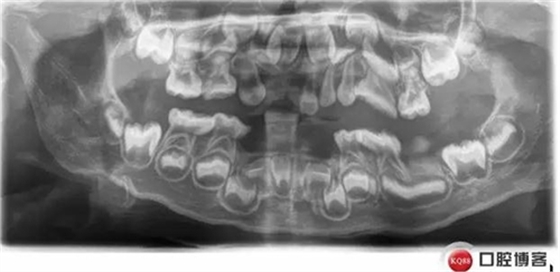

患兒,女,四歲,主訴:牙齒缺失數(shù)月,

現(xiàn)病史:患者家屬述患兒牙齒近一年多來陸續(xù)脫落要求口腔檢查來我院就診

既往史:否認(rèn)系統(tǒng)性疾病及過敏史,家族史:姐姐存在類似情況,未查明原因

檢查:12 11 21 42 41 31 32缺失,22三度松動,后牙牙齦紅腫,全口衛(wèi)生條件較差

診斷:12 11 21 42 31 32牙列缺損,22松動牙

牙齦炎

患兒檢查發(fā)現(xiàn)堿性磷酸酯酶低,確診低磷脂酶癥

低磷脂酶癥是一種罕見的遺傳代謝異常,缺乏組織非特異性堿性磷酸酶活性,口腔表現(xiàn):牙齒萌出遲緩,乳恒牙均易早失,脫落牙齒的牙根長度無變化。乳前牙最易受累而早失。病程中無明顯疼痛,牙周無明顯炎癥。X線片示牙釉質(zhì)正常,髓腔和和根管增大,牙槽骨有吸收。